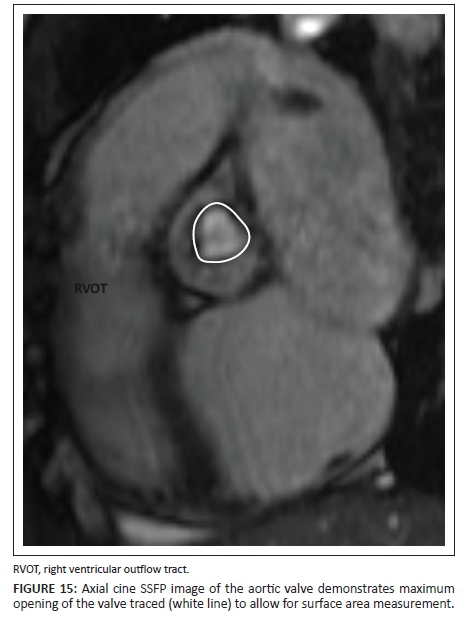

Stenosis

In patients with valvular stenosis, dephasing or a flow jet can be seen distal to the valve (Figure 14). Smaller openings, characteristic of severe disease, cause more dephasing and a darker jet is seen. The phase contrast images in severe stenosis will also demonstrate higher velocities, which will be seen as an area of complete signal loss owing to aliasing if it is above the programmed maximum velocity. This will result in an underestimation of the peak velocity as velocities higher than the programmed maximum velocities cannot be detected. In these instances, the programmed maximum velocity needs to be adjusted until the aliasing artefact disappears. The area of maximum opening of the valve can also be measured on the axial SSFP cine images through the valve (Figure 15).